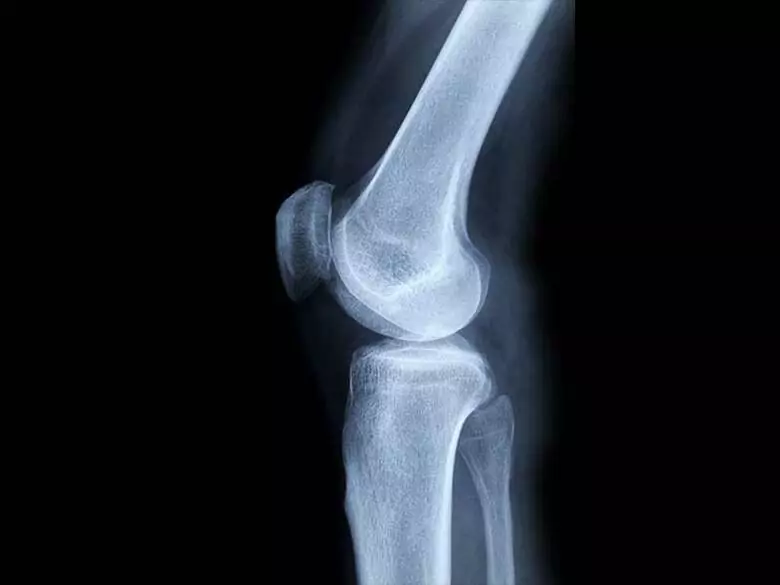

Aunque no es el tipo de cáncer más frecuente, se trata de una enfermedad muy maligna que se desarrolla rápidamente y da metástasis. Los tumores óseos malignos primarios son difíciles de diagnosticar. Debido a su localización y a sus causas conocidas, no se pueden indicar medidas preventivas.